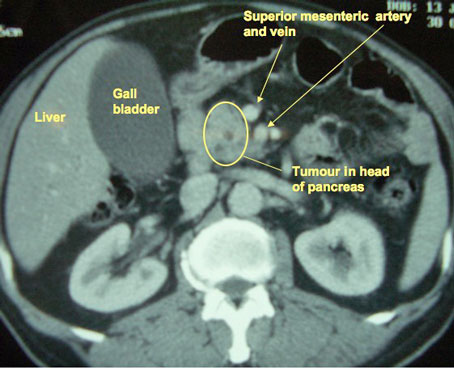

CT scan showing a tumour of the pancreatic headBlood tests generally include liver function tests and the blood level of the tumour marker CA 19-9. The latter is a substance released by some pancreatic cancers. It can be raised in other conditions too, so it is not a foolproof way of diagnosing this cancer, but it is useful to know if the levels are high to begin with, as it can help us monitor progress later on.

CT is the current “gold standard” test in most centres. It should be done with intravenous contrast given at the time of the scan.